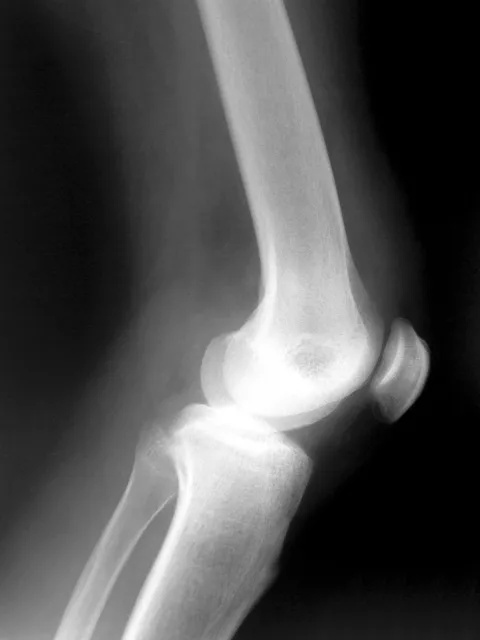

X-ray of knee